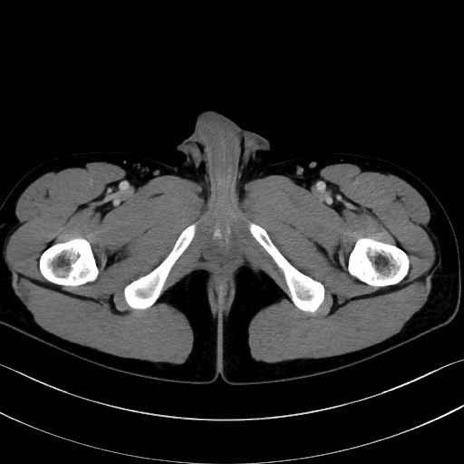

内閉鎖筋 (Obturator internus)